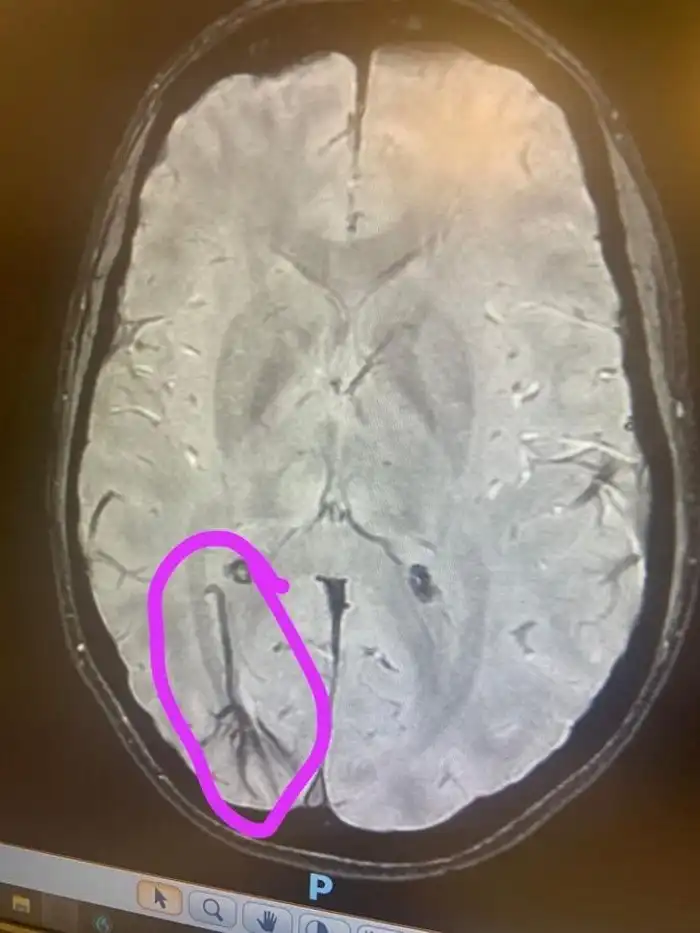

9. «На сканировании врач обнаружил вену пуповины у меня в мозгу. Она должна была исчезнуть до рождения. Теперь у меня есть оправдание, когда я веду себя по-детски»